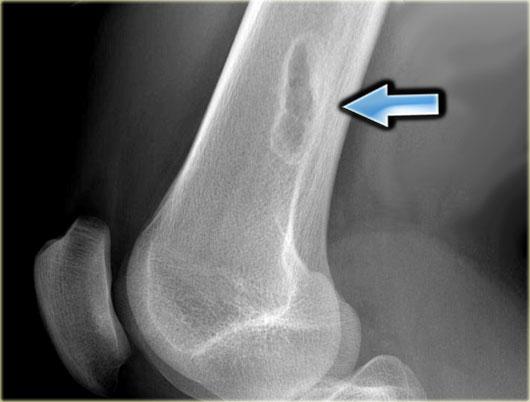

SBC: well-defined osteolytic lesion without expansion of the proximal meta-diaphysis of the humerus with pathologic fracture

Solitary Bone Cyst

Nang xương đơn độc, còn được gọi là nang xương đơn buồng, là một nang xương thực sự.

Nhiều tổn thương tiêu xương giới hạn rõ thường được gọi là dạng nang, nhưng đây là cách gọi không chính xác.

Nang xương đơn độc thường biểu hiện bằng gãy xương.

Đôi khi có thể thấy hình ảnh mảnh xương gãy rơi xuống (fallen fragment).

Vị trí hay gặp: đầu trên xương cánh tay và xương đùi.

Thường ít giãn nở hơn so với nang xương phình mạch.

Chẩn đoán phân biệt: nang xương phình mạch, loạn sản xơ dạng nang.

Nang xương đơn độc có thể di chuyển từ vùng hành xương đến thân xương trong quá trình phát triển của xương.

Discriminators:

- Must be under age 30.

- Must be centric